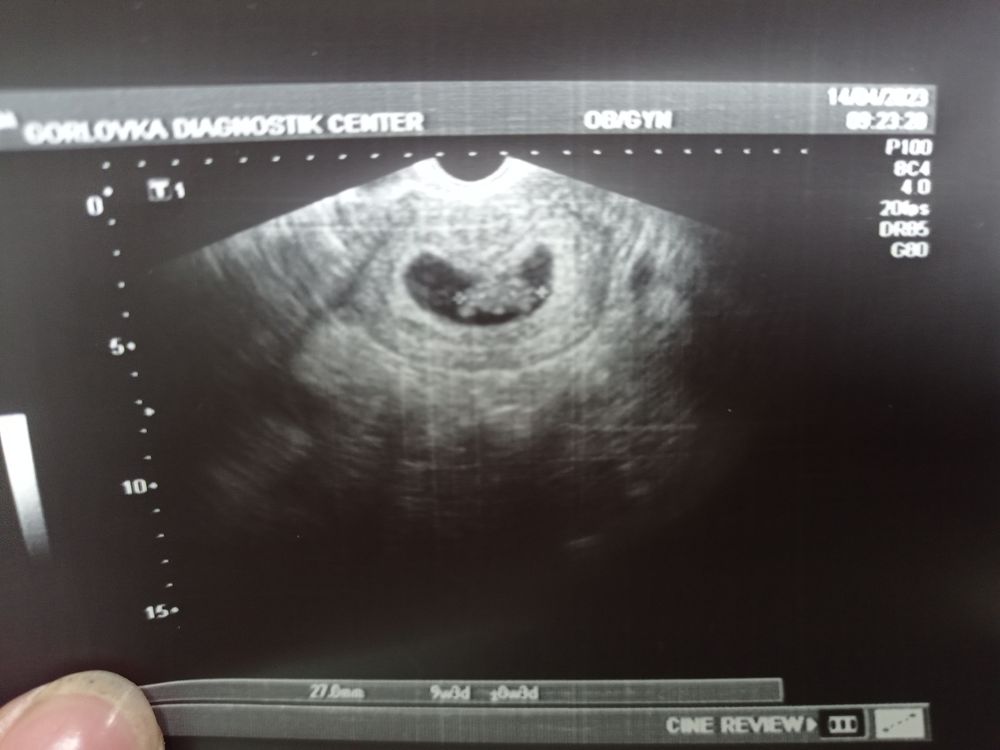

Изображение А какой у вас КТР? У меня в 9 и 3 на УЗИ за ручки и ножки вообще ничего не сказали, единственное,что сказали:"только начало все развиваться, ничего не видно,увидите все на скрининге "😅 Я даже не понимаю,как он лежит,у вас правда фото по ближе ..

Marina, у меня на 9 и 3 было 27 мм. Не знаю, возможно) меня посмотрели от силы минуты 3,хотя и в платную ходила,но была очередь,погоня за деньгами,видимо 😂

Маша, это все узи сегодня, сделали просто 3 фото) Изображение На этом фото тоже не понятно где и что😂